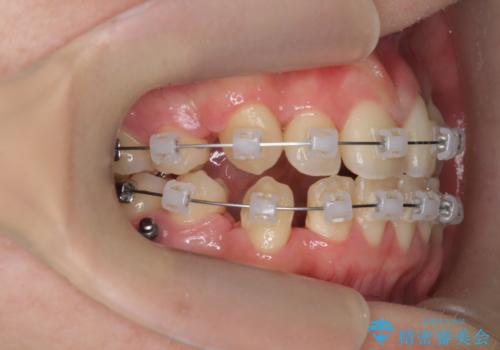

歯並びのせいで歯ブラシがしづらい マルチブラケットを用いた抜歯矯正

- 歯並びのがたつきにより歯ブラシがしづらく、今後虫歯になってしまう不安から、矯正治療を希望されて来院されました。

歯を並べるにはスペースが不足しているため、小臼歯の抜歯を4本行うマルチブラケット矯正による治療を計画します。

治療後は非常に歯ブラシがしやすくなったと、治療結果に満足いただくことができました。